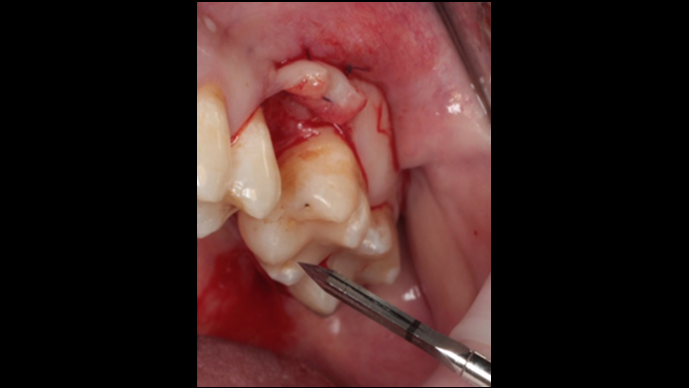

“Thin ridge expansion with minimally invasive surgery!

Use SmarThor & AnyRidge to place a wider diameter implant with minimal drilling after ridge splitting, even in thin ridge under 2mm! “

Clinical case: Ridge splitting technique using SmarThor + AnyRidge as expander

- Courtesy of Dr.Kwang-Bum Park, Korea -

Keywords

AnyRidge, ridge splitting, GBR, Dr. Kwang-Bum Park, mandibular posterior, SmartThor, Mega-Oss, thin ridge, bone regeneration

Products:

AnyRidge implant system. SmarThor, Mega-Oss